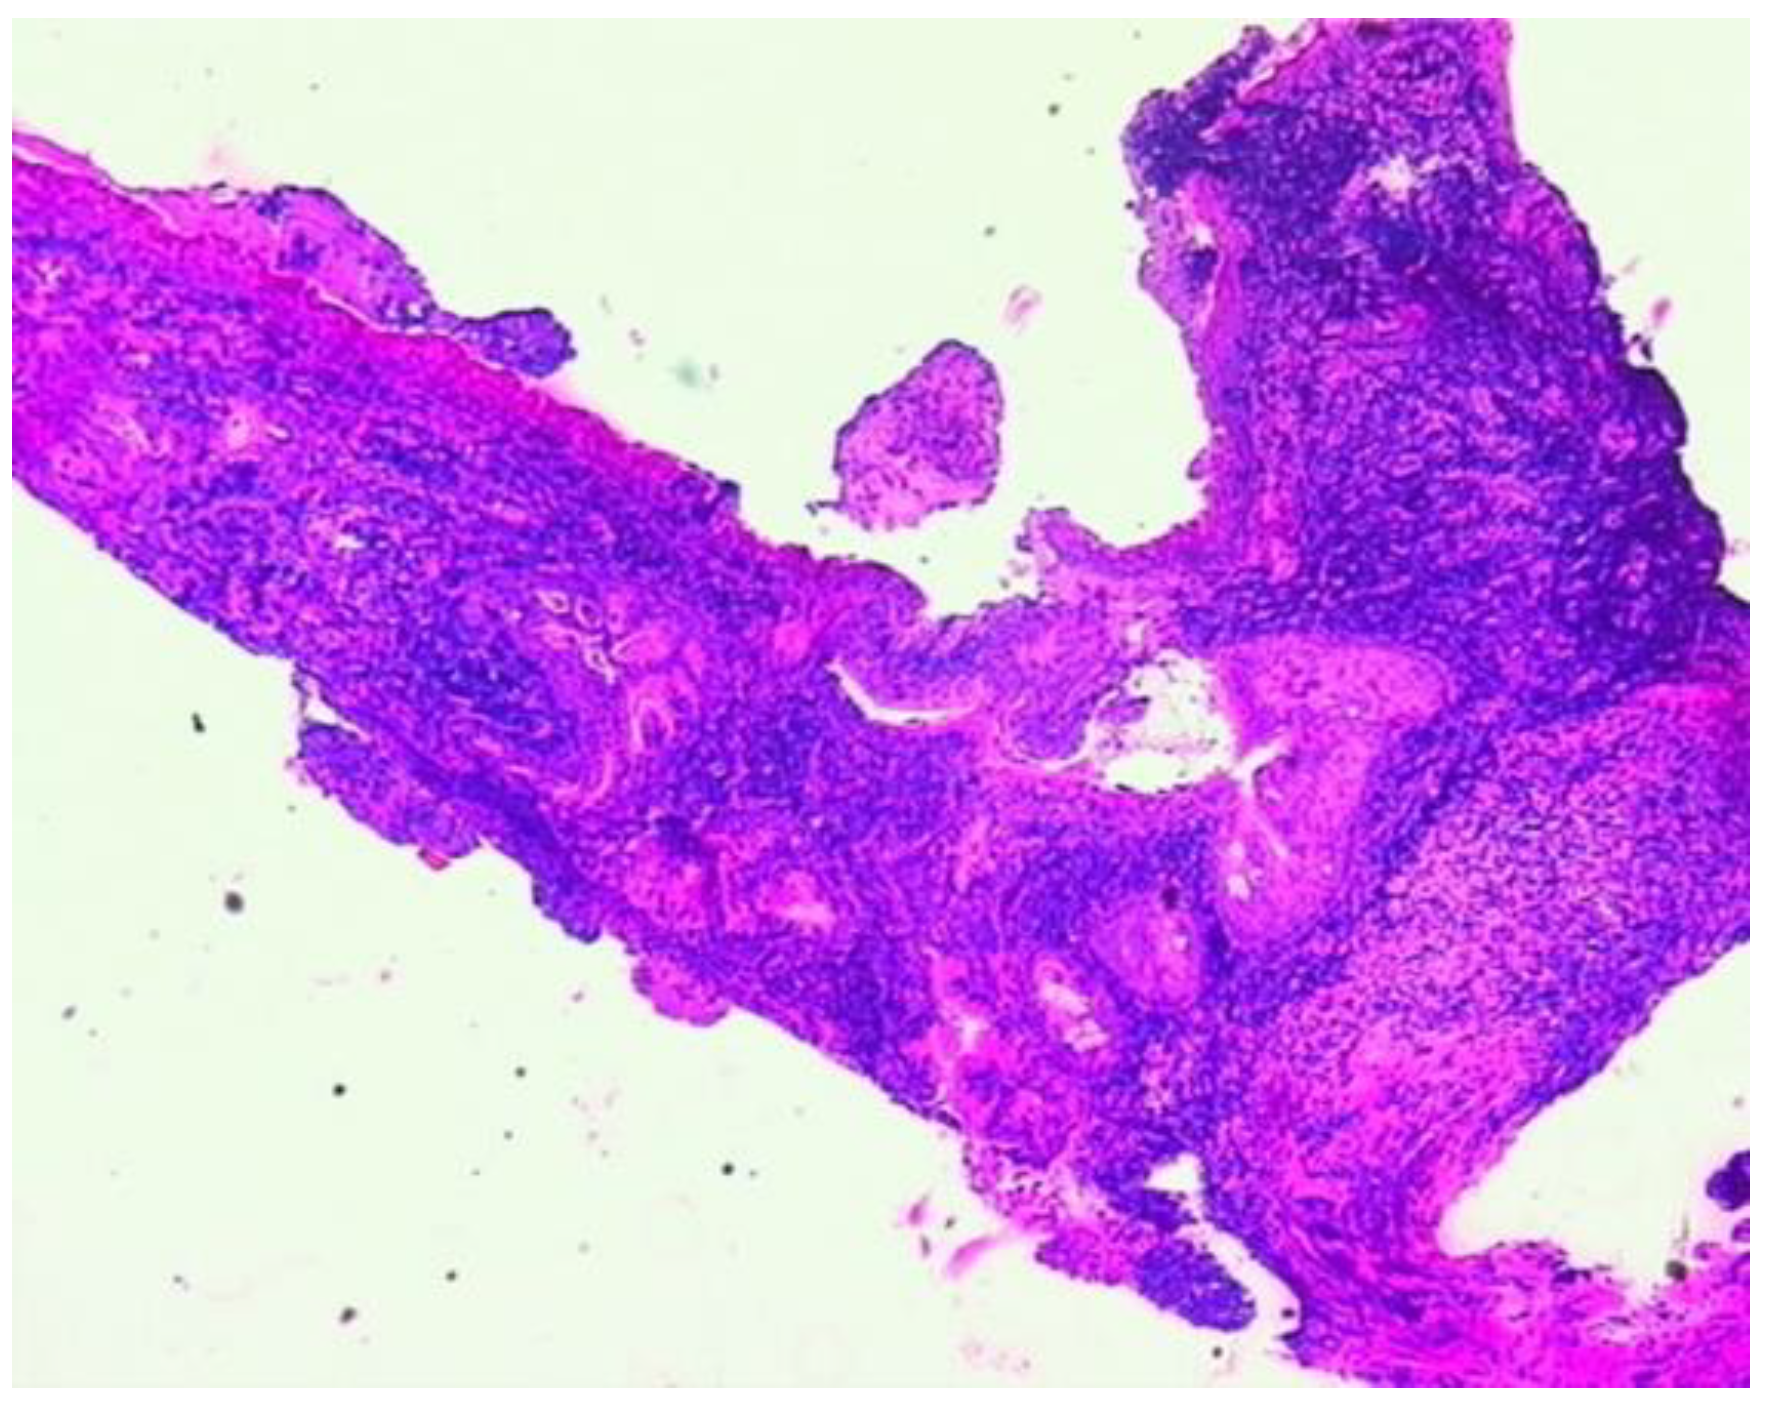

3.2.1. A Fine Index of Clinical Suspicion: Low Back Pain